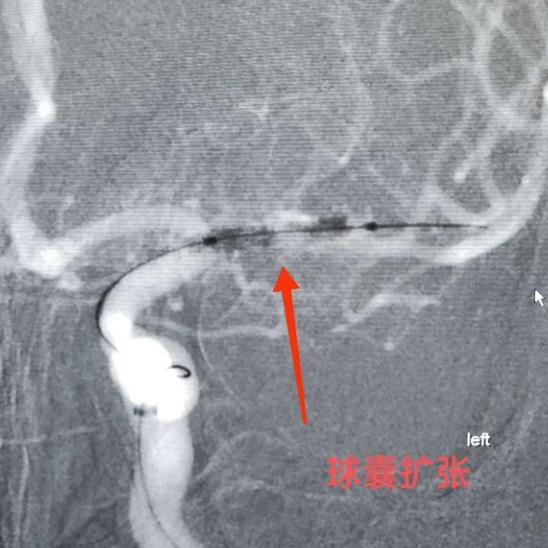

??球囊扩张狭窄段